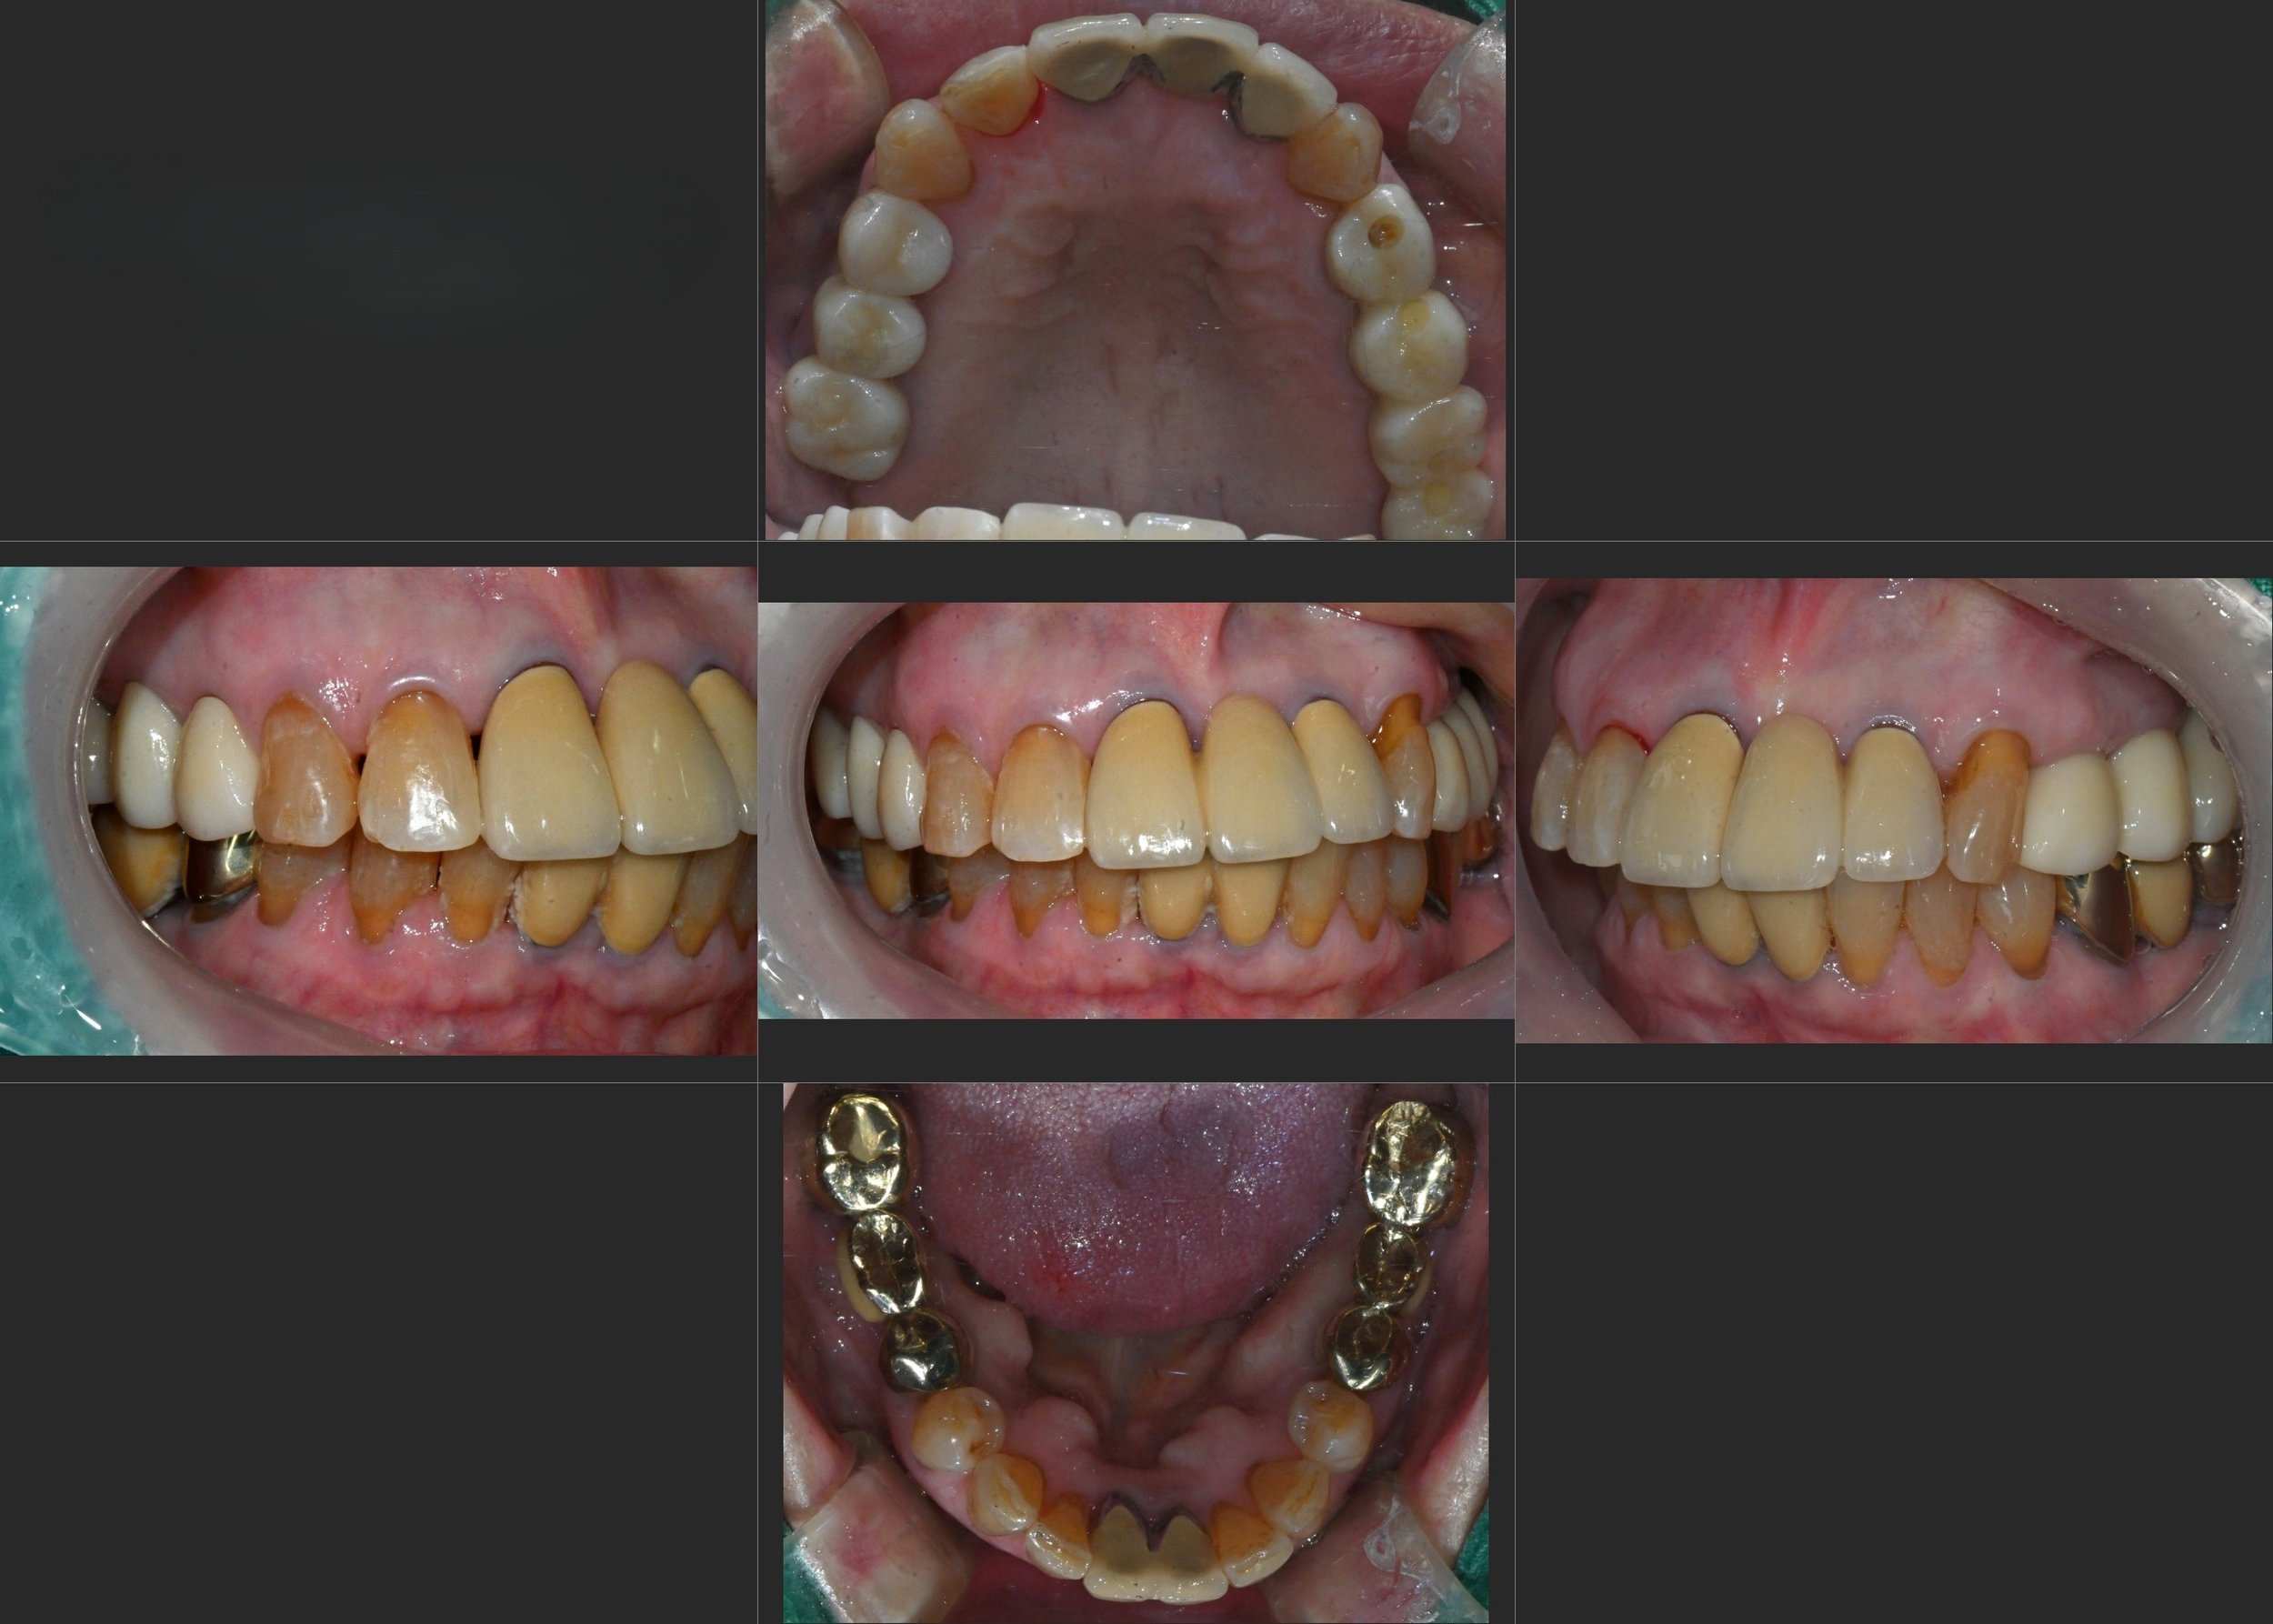

INTRA ORAL - BEFORE

Treatment Objectives

• Resolution of maxillary sinus pathology

• Elimination of unilateral mastication pattern

• Restoration of fractured teeth and compromised dentition

• Recovery of occlusal vertical dimension to prolong anterior tooth longevity